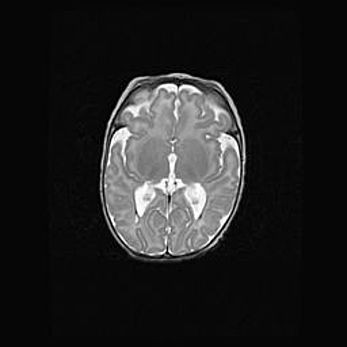

Открытая гидроцефалия.

Возраст: 6 месяцев 15 дней

Вес: 6200 г

Пол: женский

Окружность головы: 41 см

Срок гестации: 38 недель

Гидроцефалия головного мозга у новорожденных – это скопление избыточного количества цереброспинальной жидкости в головном мозге. Ее избыточное скопление в мозге приводит к патологическому расширению желудочков мозга (четырех полостей, расположенных в глубине белого вещества мозга, заполненных цереброспинальной жидкостью и связанных узкими проходами).

Открытый тип гидроцефалии (сообщающаяся) наблюдается тогда, когда нарушен механизм всасывания ликвора в системный кровоток. При этом типе причиной заболевания чаще всего является перенесенные ранее инфекции (например: менингит),  либо же наличие крови в субарахноидальном пространстве.